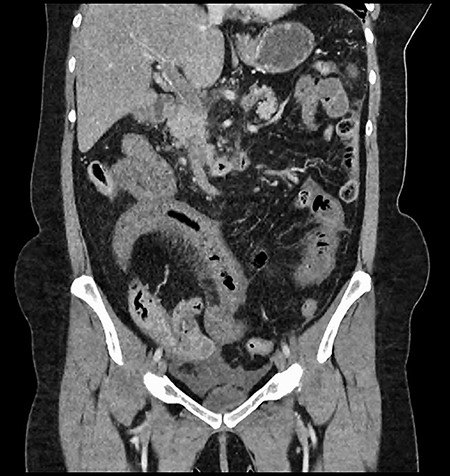

A 61-year-old female presented to a regional hospital with a 3-week history of intermittent diarrhoea, vomiting and generalized abdominal pain. She had a diffusely tender abdomen but was not peritonitic, and was shocked with a heart rate of 110 beats per minute, blood pressure of 89/45 mmHg and was peripherally cool. Her blood tests revealed a lactate of 7.2 mmol/L, which worsened to 7.8 mmol/L during resuscitation with intravenous fluids, and white cell count was 30.9 × 109/L, with an international normalized ratio (INR) of 1.4. She had an acute kidney injury with a creatinine of 119μmol/L and estimated glomerular filtration rate (eGFR) of 43 mL/min/1.73m2. Computed tomography (CT) revealed extensive thickened loops of non-enhancing small bowel with pneumatosis, moderate free fluid and a large splenic infarction. There was extensive thrombosis of the splenic vein and superior mesenteric vein extending into the portal vein to the level of the porta hepatis. Her background history included factor V Leiden and protein S deficiency, for which she had been non-compliant with warfarin during this illness. She had no surgical history (Figs. 1–5).

CT showing multiple thick-walled, non-enhancing loops of small bowel.